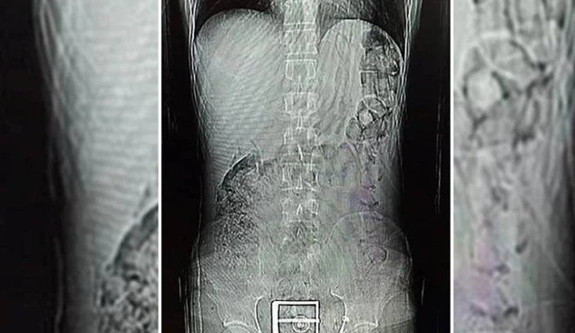

Şüphelinin, götürüldüğü hastanede çekilen mide ve bağırsak röntgen çekimlerinde, çok sayıda yabancı cisim tespit edildi.

Tıbbi müdahaleyle şüphelinin vücudundan 78 kapsül halinde 603,35 gram Afyon sakızı, 17 kapsül halinde 111,35 gram sentetik uyuşturucu çıkarıldı.